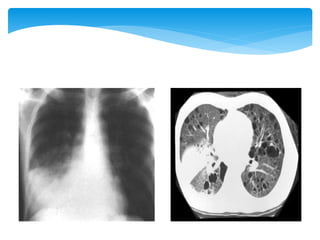

COPD : -Chronic Bronchitis (Chronic inflammation of the mucous membrane in the bronchial passages causing the membrane and the mucus to thicken making it hard to breathe (SOB) because the air cannot pass through easily. It leads to SOB). Acute (lasting less than 6 weeks). Chronic (recurring for more than a year). Mostly viral. Tobacco, Coal miners, grain handlers, metal holders, dust etc…

- Emphysema (Destructionof the lung tissue around the bronchioles causing these airways to collapse preventing the air to come out during exhalation. The chest wall muscles have to work harder to expel the air. There is also damage of the walls between many of the air sacs. As a result, the air sacs lose their shape and become floppy causing a reduction in the amount of gas exchange in the lungs. Tobacco, alpha-1 antitrypsin, air pollution, heredity etc..